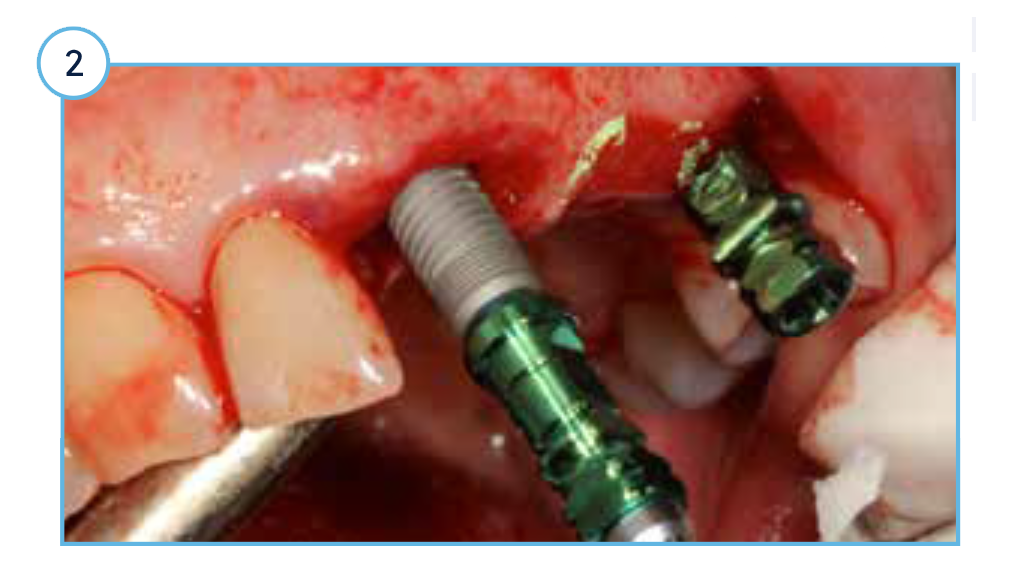

Radiographic view at the time of placement with surgical cover screws attached.

One-year post-placement radiograph with stable marginal bone levels around TSVT implants.